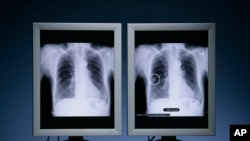

یک پژوهش جدید نشان داده که «ایمنی درمانی»، به علاوه «شیمی درمانی»، عمر بیماران متبلا به سرطان ریه را طولانی تر می کند. در «ایمنی درمانی»، سیستم ایمنی خود بیمار وادار به واکنش در برابر سلول های بدخیم می شود.

سرطان ریه یکی از رایج ترین سرطان ها است، اما تلاش ها برای افزایش طول عمر بیماران متبلا به سرطان ریه چندین دهه است که پیشرفت اندکی داشته است.

سرطان ریه در سطح جهان سالانه باعث مرگ ۱ میلیون و ۷۰۰ هزار نفر می شود و در آمریکا انتظار می رود در سال ۲۰۱۸ بیش از ۱۵۴ هزار نفر در اثر ابتلا به این نوع سرطان جان دهند.